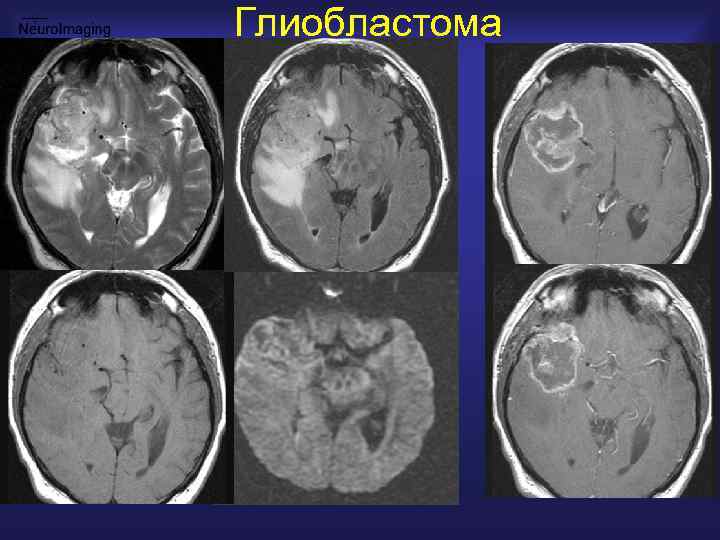

Глиобластома